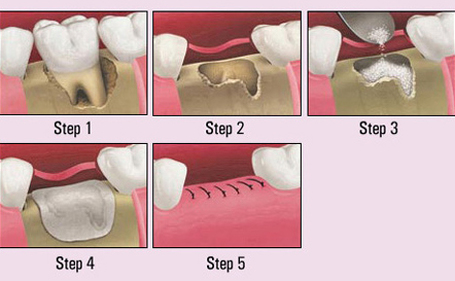

Dental care is medically necessary to prevent and eliminate orofacial diseases, infections and pains, to restore the shape and function of the dentition and to correct facial disfigurement or dysfunction. The term clinical medical necessity is also often used.

Can I get implants with bone loss?

Even if you’ve lost all your teeth and noticed your cheeks starting to sink inward, a sign of jaw bone loss, you may still not need a bone graft to support your dental implants. During your initial consultation, your dentist will take 3D images of your mouth, including your jaw.